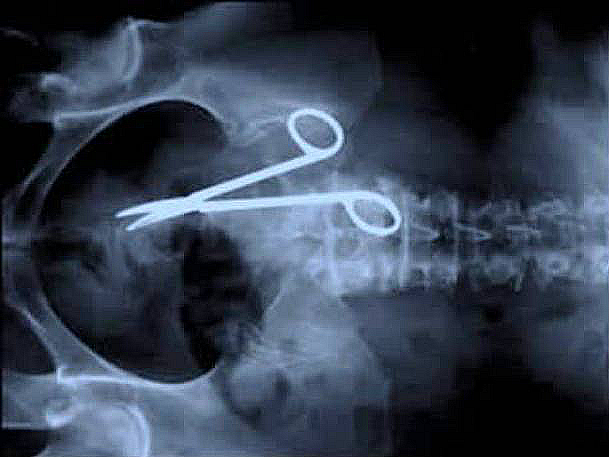

Surgical scissors

viralscape.com

Image Source: viralscape.com

An Australian man came back to the hospital 18 months after a surgery complaining about stomach aches. You can imagine everyone's reaction when they discovered that the doctors have forgotten surgical scissors in this poor man's abdomen.